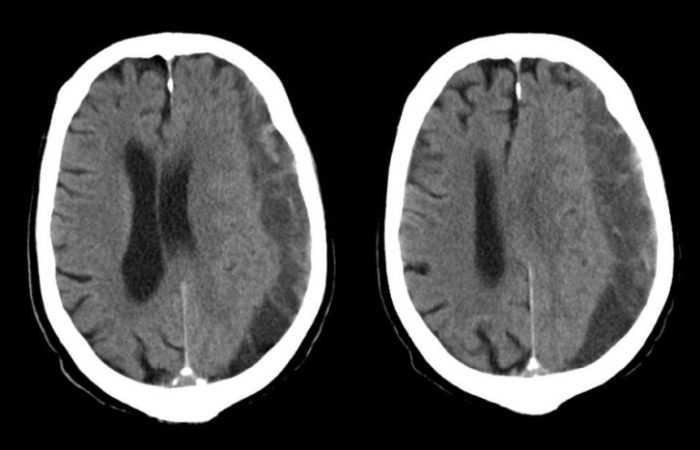

Setelah mengetahui gejala dan penyebab hematoma subdural, langkah selanjutnya adalah melakukan diagnosis dan pengobatan yang tepat. Diagnosis hematoma subdural biasanya dilakukan melalui pemeriksaan fisik dan tes pencitraan, seperti CT scan dan MRI. Pengobatan hematoma subdural tergantung pada tingkat keparahannya, mulai dari observasi hingga pembedahan.

- CT Scan (Computed Tomography Scan): CT scan merupakan prosedur yang menggunakan sinar-X untuk menghasilkan gambar potongan melintang otak. CT scan dapat menunjukkan lokasi, ukuran, dan bentuk hematoma subdural. CT scan juga dapat menunjukkan adanya kerusakan otak lainnya, seperti edema atau perdarahan. CT scan merupakan pemeriksaan yang cepat dan mudah dilakukan, dan hasilnya dapat diperoleh dalam waktu singkat.